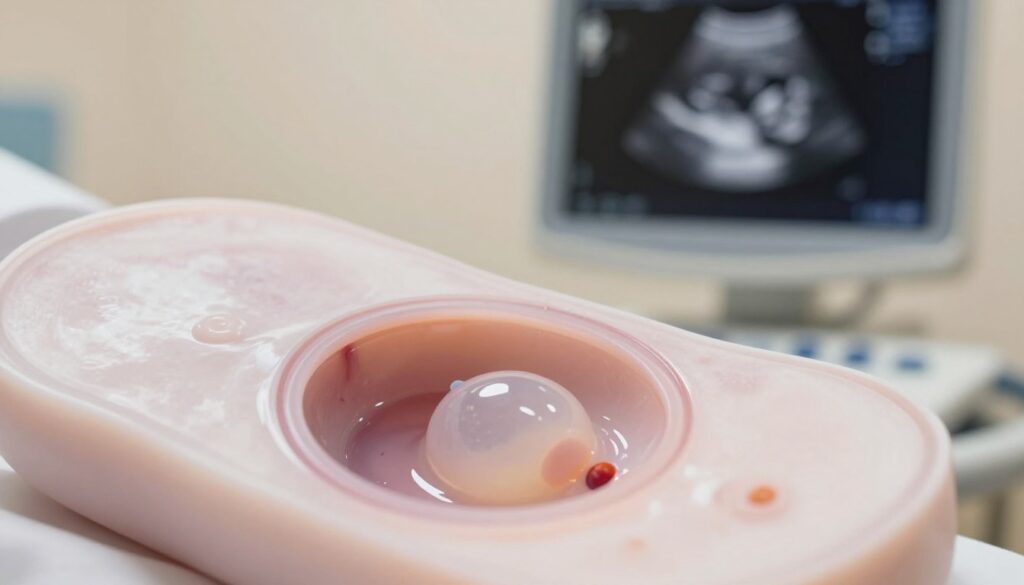

4. tydzień — pęcherzyk ciążowy (GS) może być już widoczny. Na początku ma zwykle 1–4 mm. Rosnący pęcherzyk zwiększa się ~1 mm na dobę. Obecność okrągłej lub owalnej struktury potwierdza lokalizację ciąży.

5.–6. tydzień — pęcherzyk żółtkowy pojawia się zwykle gdy GS osiąga 8–10 mm. YS ma typowo 2–3 mm i stopniowo rośnie do ~6 mm. Pełni funkcję „spiżarni” dla rozwijającej się ciąży.

Po pojawieniu się YS zarodek zwykle pojawia się 1–2 dni później, najczęściej wzdłuż brzegu pęcherzyka żółtkowego. W praktyce krótkie różnice dni mogą znacząco zmienić opis obrazu.

| GS (pęcherzyk) | ok. 4 tyg. +5 dni | 1–4 mm, +1 mm/dzień | Potwierdza lokalizację |

| YS (pęcherzyk żółtkowy) | 5–6 tyg. | 2–3 mm → do 6 mm | Wczesne wsparcie metaboliczne |

| Zarodkowa struktura | po YS, +1–2 dni | widoczna przy większym GS | Ocena rozwoju i bicia serca |